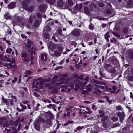

To deal with some of the aforementioned issues, we introduce a new approach for simultaneous H&E stain normalization and augmentation based on the multimarginal Wasserstein barycenter approach. Specifically, the novelty of the paper lies in first introducing the traditional Wasserstein barycenter approach for stain normalization/augmentation (Figure 1), and then introducing the multimarginal version [1, 9] to overcome the limitations of the traditional approach in this context (Figure 2). Note that the traditional Wasserstein barycenter (1 source and 1 reference), although widely employed in computer vision, to the best of our knowledge has never been used for stain normalization/augmentation and the more general multimarginal Wasserstein barycenter (1 source and multiple references) has hardly ever been used in computer vision or medical imaging communities. For more accurate stain normalization, the multimarginal version allows one to incorporate additional distributions by utilizing one or more intermediate reference images (Figure 2). The resultant interpolations span a broad spectrum of stain variations allowing for simultaneous stain normalization and augmentation.

The case is classical due to McCann [8] has been sketched in Section 2. For our purposes for stain normalization and augmentation in histological data, we may regard as the source distribution and as the reference distribution. Then for , we can consider minimizing the family of functionals

and hence get a continuous family of interpolations which form a geodesic in the space of probability distributions as described in Section 2. See equation (4).

In the present work, we also employ one source distribution and either or reference distributions (). For in (6), i.e., two or more references, we use the term “multimarginal OMT,” to emphasize the fact that we are considering more than two measures. For the application to images, one can always normalize to make sure that the total mass (intensity) is 1.

Further in the examples below (see Section 4), we choose , . Let denote the optimal solution of (6), that is, the barycenter. Notice that taking and as the marginals, we also find the optimal transport map We also set the parameter , which is the number of intermediate reference images. Thus, refers to the usual Wasserstein barycenter computed with respected to a reference and a source, with no intermediate reference images.